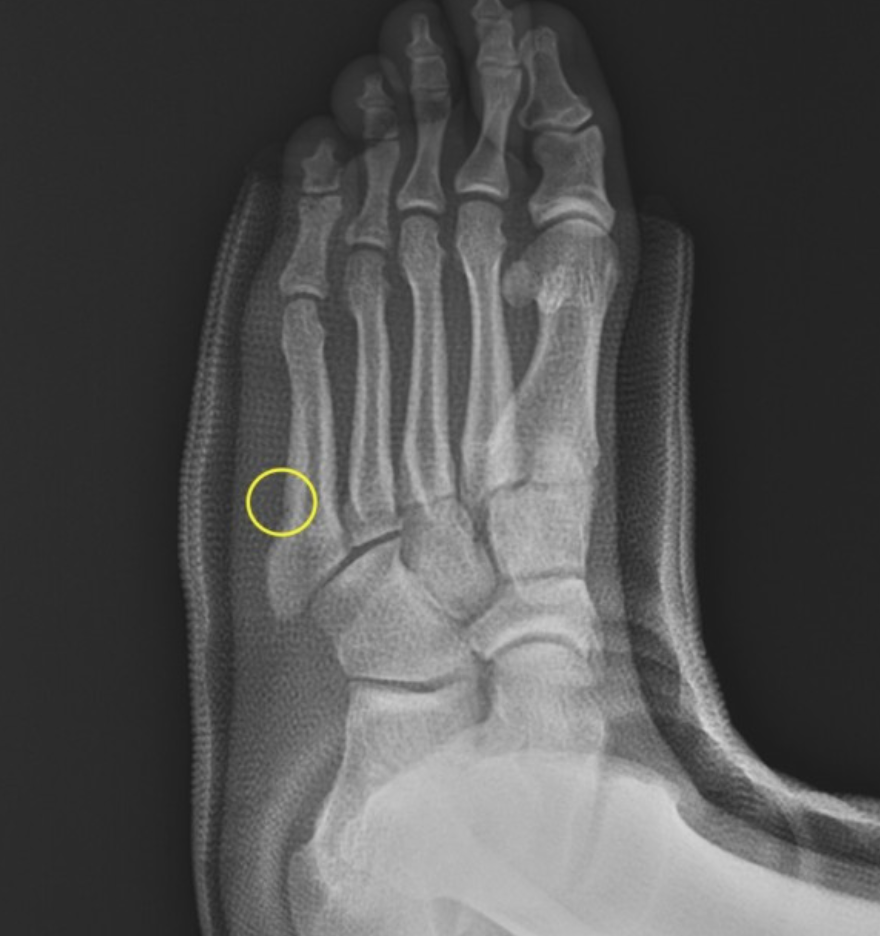

중족골(Metatarsal)은 발등에서 발바닥까지 뻗어 있는 뼈로, 달릴 때 지면과 접촉하면서 충격을 받는 부위입니다.

이 부위에 골절이 생기면 단순히 ‘발이 아픈’ 수준을 넘어서 걷기조차 힘들고, 장기적인 후유증으로 이어질 수도 있습니다.

중족골 골절은 격한 충돌보다도 반복적인 피로, 점프 착지 미스, 신발 불균형 등으로 쉽게 발생합니다.